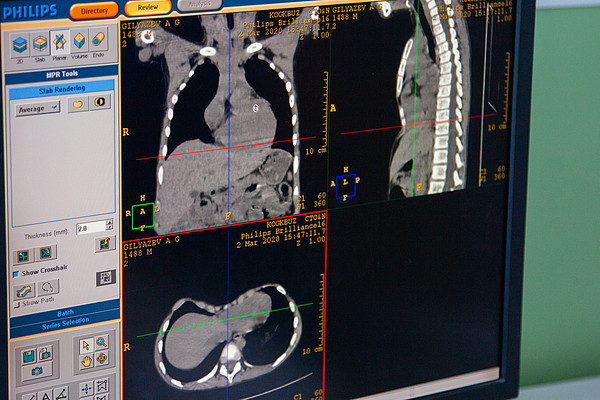

IMG_1735.